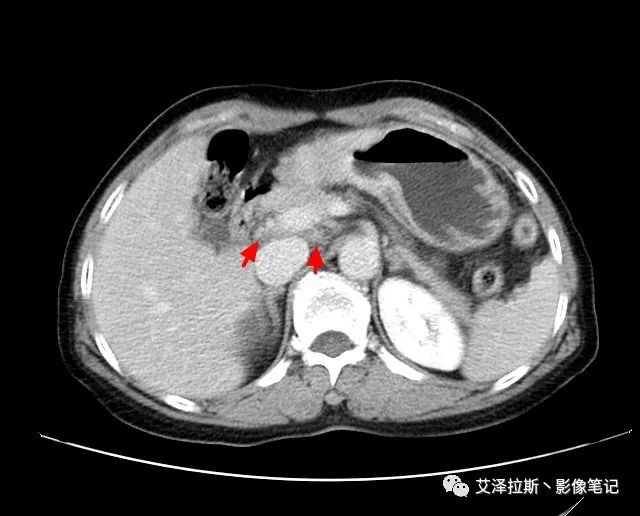

以下為累及的區(qū)域淋巴結(jié),共計15個區(qū)域:

【影像所見】 胃竇部狹窄,胃壁環(huán)形增厚,小彎側(cè)見一巨大潰瘍,周圍伴“環(huán)堤征”,漿膜面不完整,胃周脂肪見網(wǎng)格狀條索影,病灶與肝臟左葉、胰腺鉤突脂肪間隙消失,增強(qiáng)掃描病灶明顯強(qiáng)化。引流區(qū)內(nèi)約15個區(qū)域淋巴結(jié)受累。

【診斷意見】 胃竇部胃癌(T4N3期) 該病例腫塊突破漿膜層,與肝臟左葉、胰腺鉤突分界不清,脂肪界面消失,定為T4期; 受累及的淋巴結(jié)為15個區(qū)域,定為N3; 有無遠(yuǎn)處轉(zhuǎn)移尚不明確,所以M期暫時無法確定。